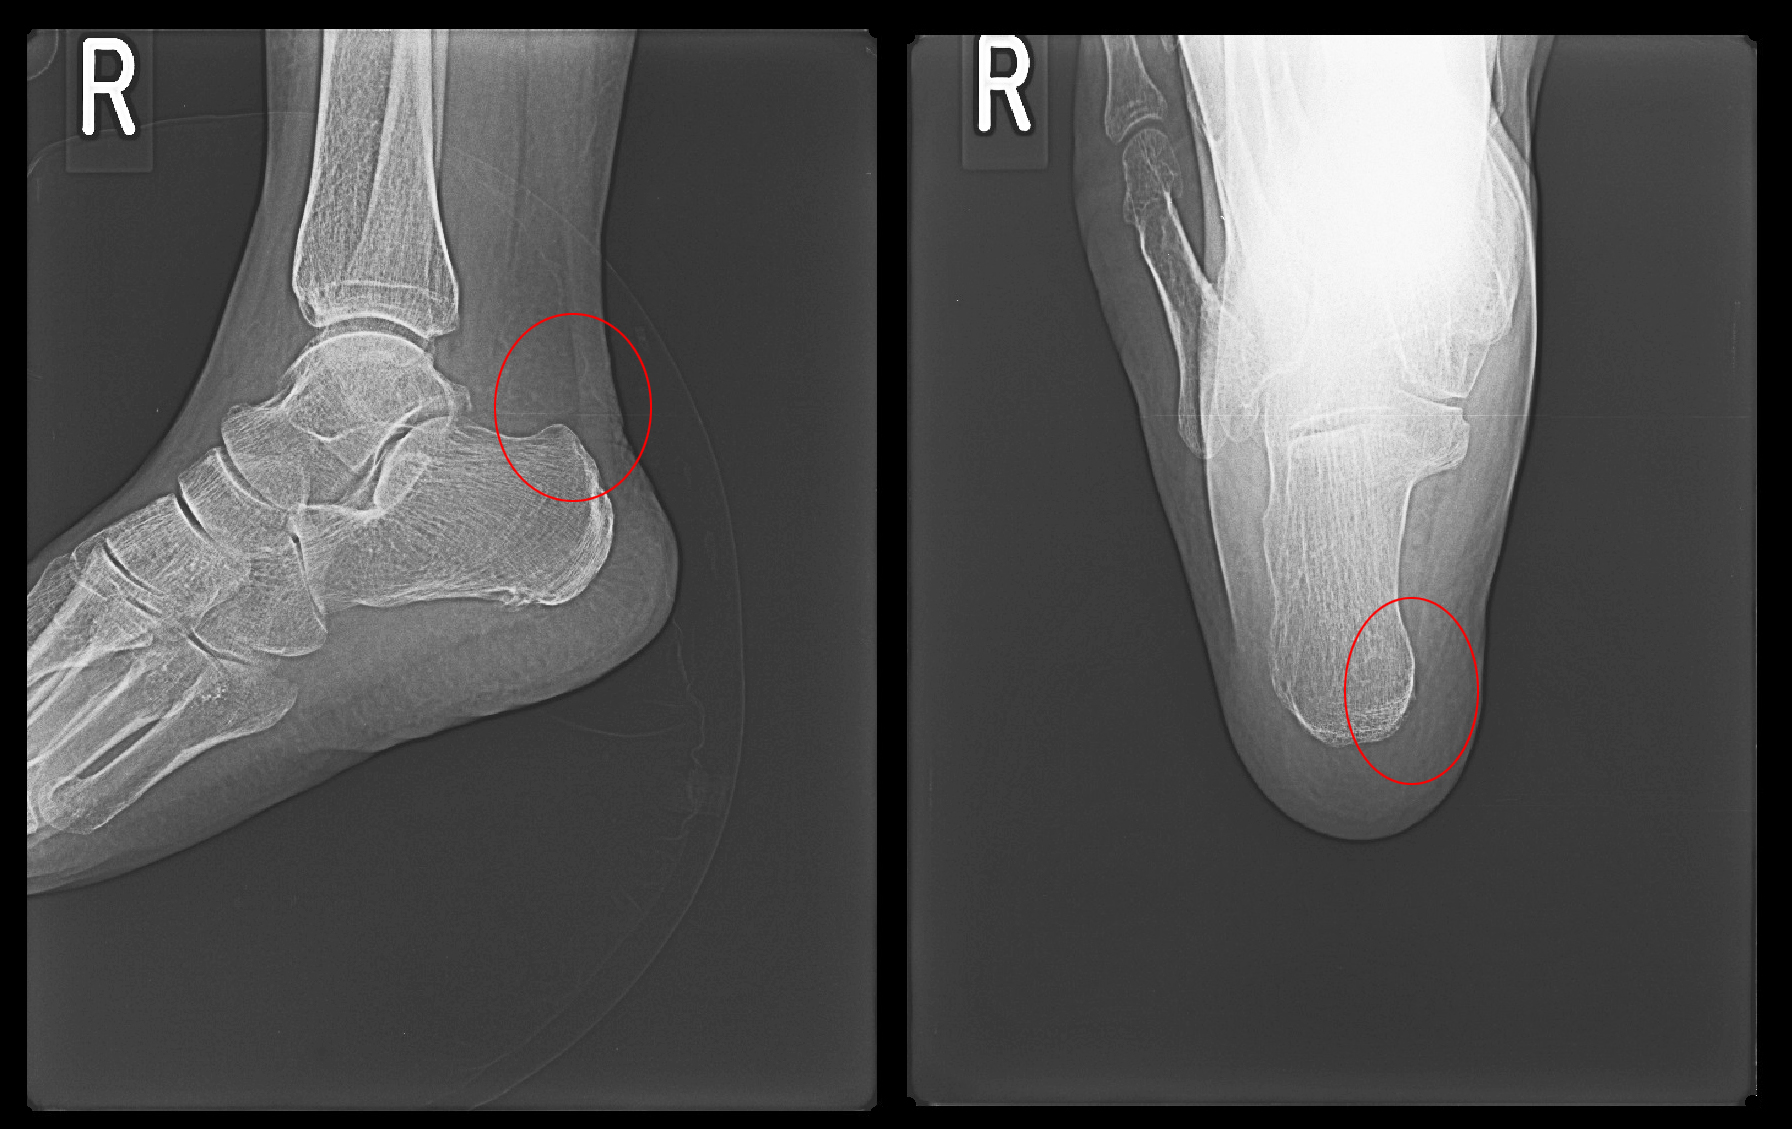

初診時Xp.jpg

MRI検査では踵骨内の足底側が白くなり(オレンジ矢印)疲労骨折ともとれますが、痛みの本質は赤矢印の足底腱膜炎によるものと判断しました。